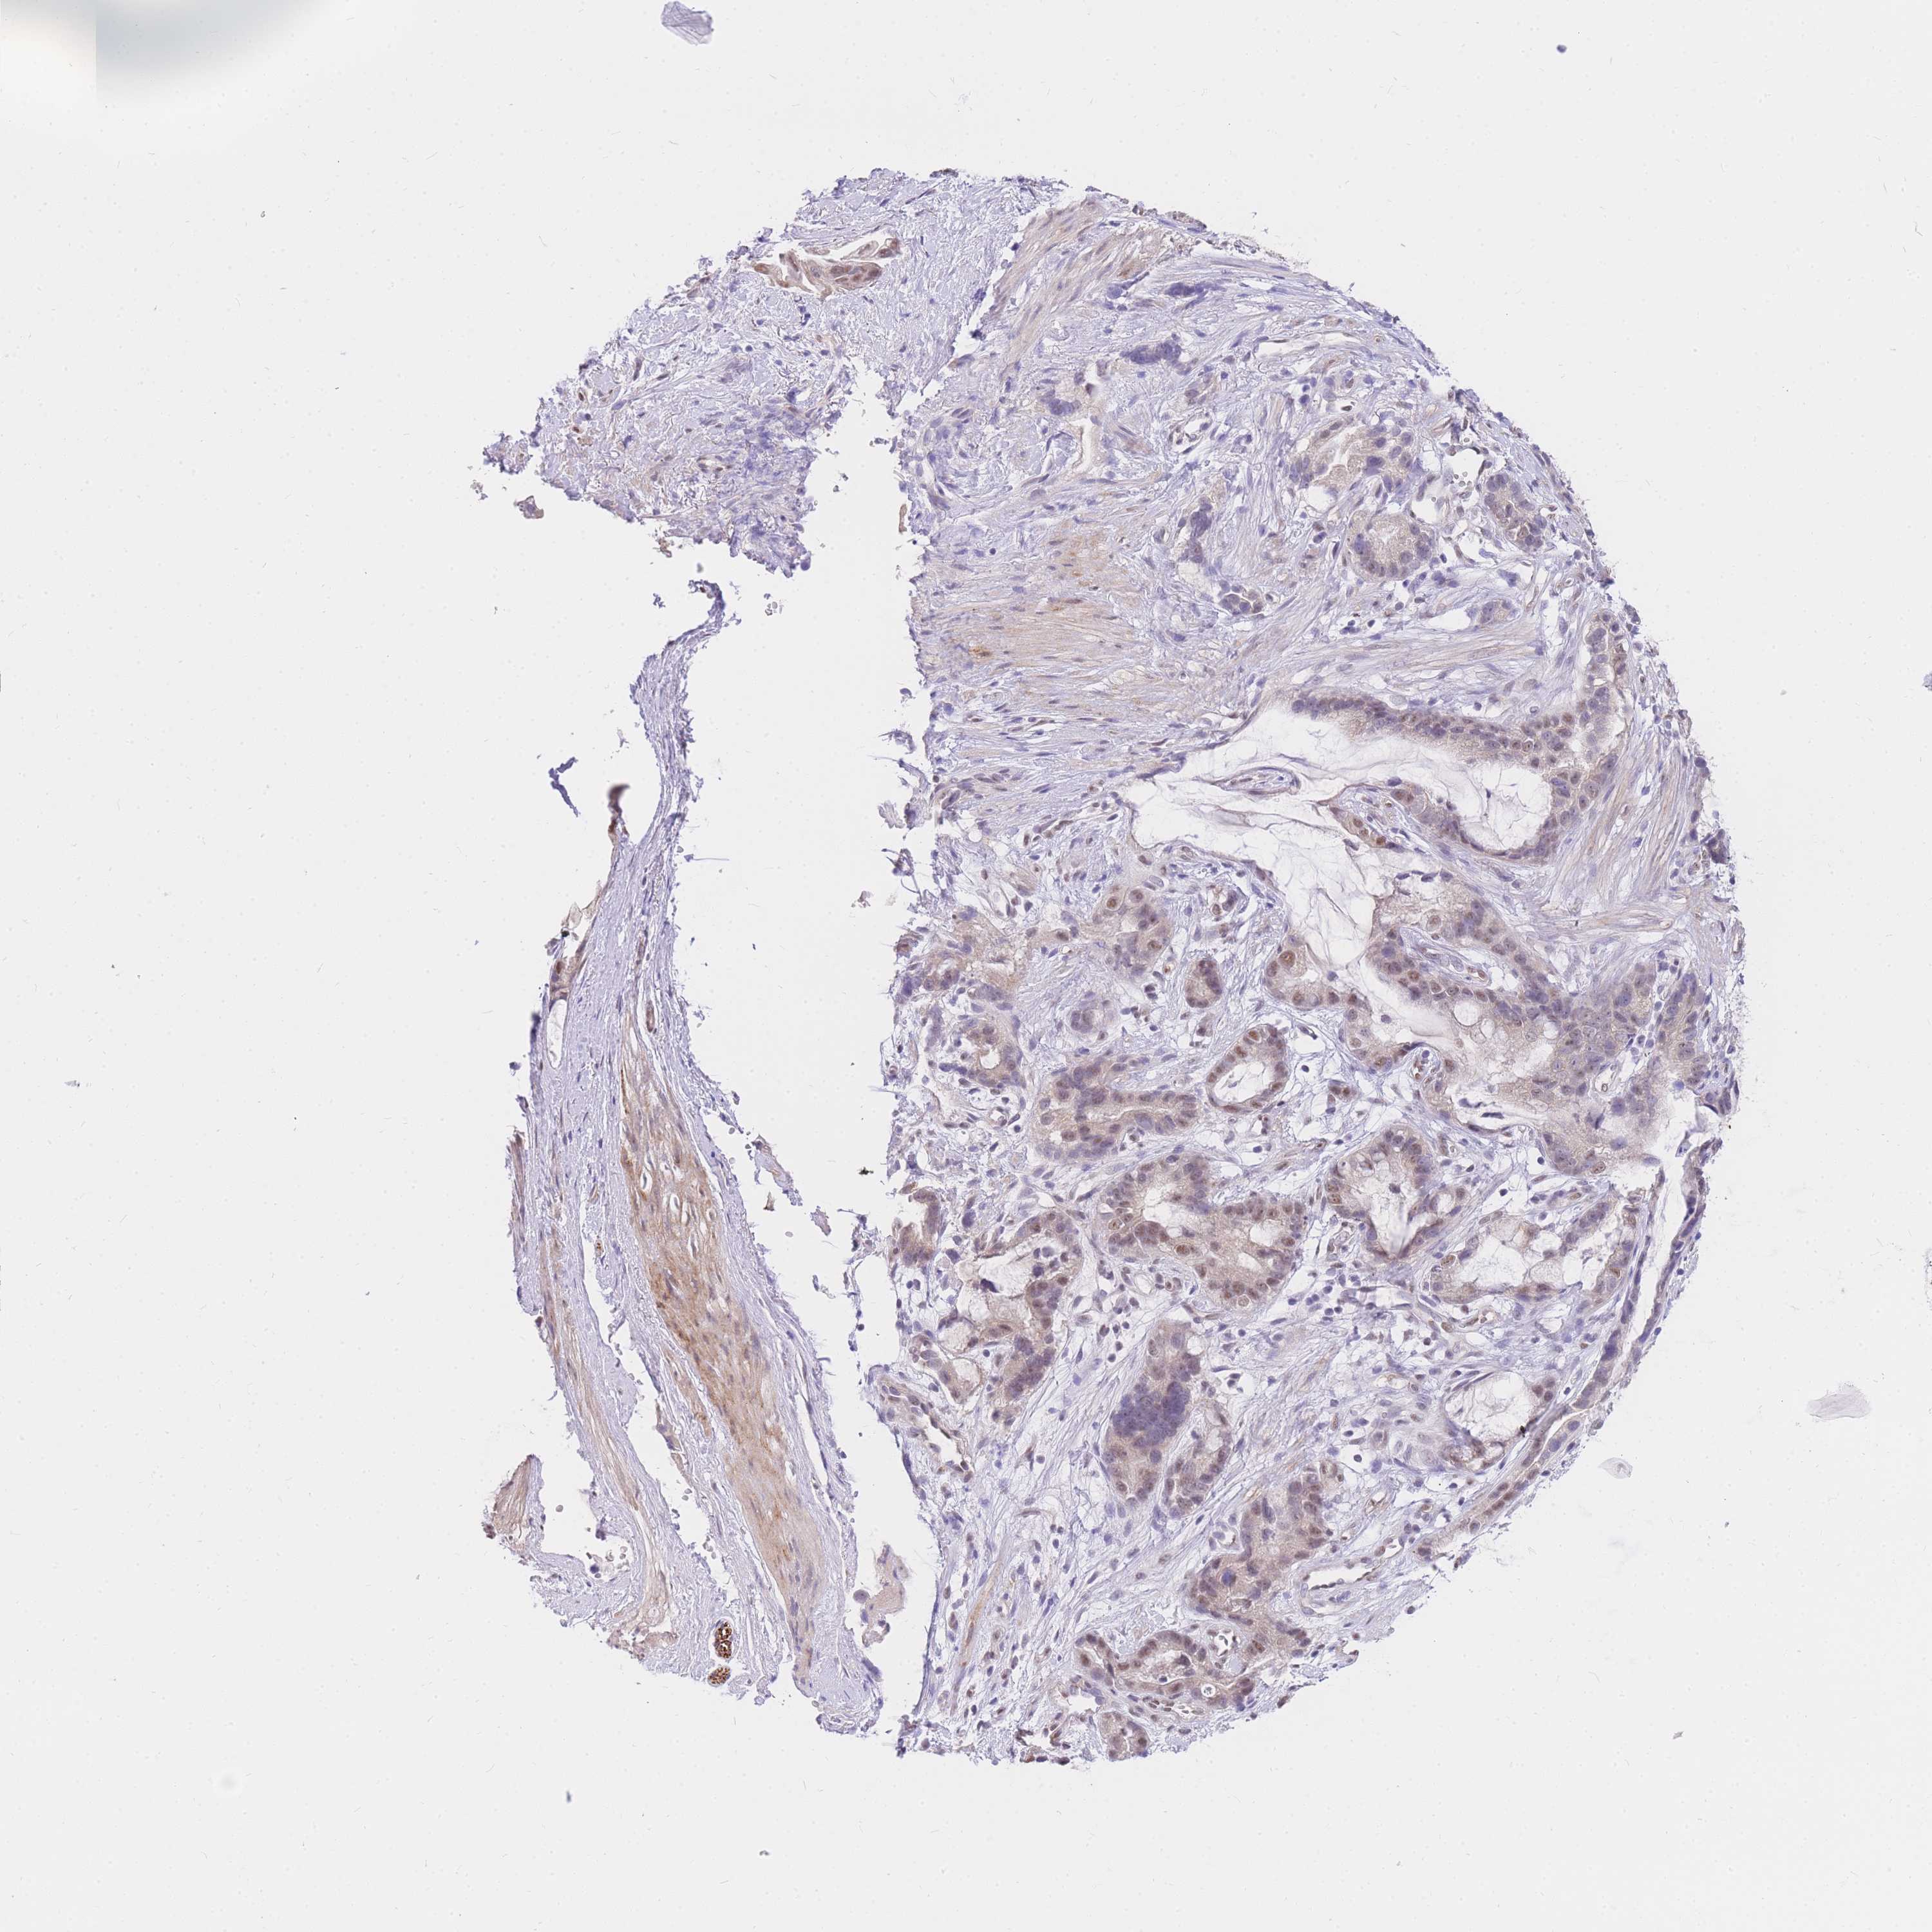

STOMACH CANCER - Protein expressioni

A mouse-over function shows sample information and annotation data. Click on an image to view it in a full screen mode. Samples can be filtered based on level of antibody staining by selecting one or several of the following categories: high, medium, low and not detected. The assay and annotation is described here.

Note that samples used for immunohistochemistry by the Human Protein Atlas do not correspond to samples in the TCGA dataset.

Antibody stainingi

Antibody staining in the annotated cell types in the current human tissue is reported as not detected, low, medium, or high, based on conventional immunohistochemistry profiling in selected tissues. This score is based on the combination of the staining intensity and fraction of stained cells.

Each image is clickable and will lead to virtual microscopy that enables deeper exploration of all samples and also displays staining intensity scores, fraction scores and subcellular localization as well as patient and tissue information for each sample.

Antibody HPA027242

Antibody HPA027328

Staining

High

Medium

Low

Not detected

Intensity

Strong

Moderate

Weak

Negative

Quantity

>75%

75%-25%

<25%

None

Location

Nuclear

Cytoplasmic/membranous

Cytoplasmic/membranous,nuclear

Adenocarcinoma, NOS